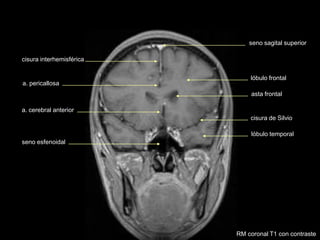

seno sagital superior

asta frontal

cisura de Silvio

lóbulo temporal

lóbulo frontal

cisura interhemisférica

a. pericallosa

a. cerebral anterior

seno esfenoidal

RM coronal T1 con contraste